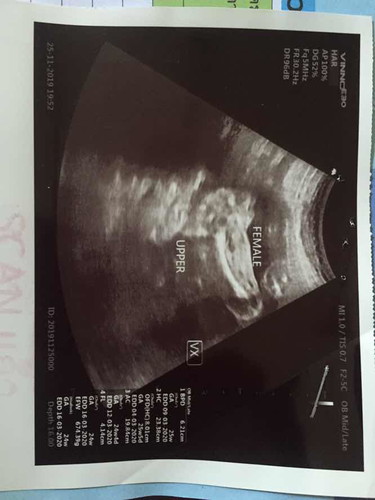

หมอบอกผู้หญิง ชัวร์มั้ยคะว่าผู้หญิง

แม่ๆบ้านไหนดูออกบ้าง อันนี้หมอซาวด์ตอน24สัปดาห์ หมอจะซาวด์อีกไหมคะ

ลูกสาวจ้าแม่